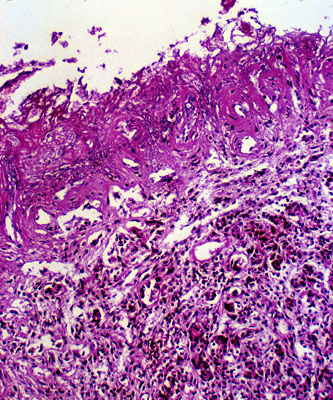

Pseudocyst, H&E.

No lining epitheilum.